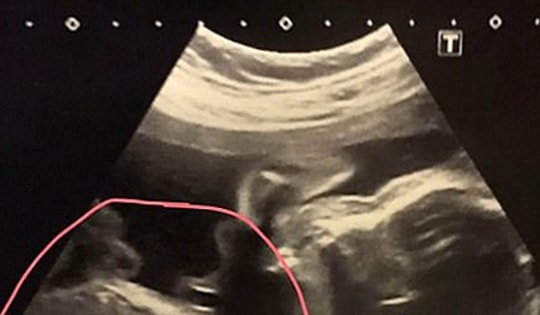

Một người phụ nữ đã trở thành một trong số chưa đến mười người trong lịch sử có thai khi đang mang thai. Câu chuyện kỳ lạ của cô hiếm đến nỗi ngay cả việc trúng xổ số cũng có khả năng xảy ra hơn.

Đi khám định kỳ, người phụ nữ sốc nặng khi phát hiện 2 bào thai trong bụng con. Bác sĩ thông tin rằng "thai trong thai" là một trong những trường hợp hiếm gặp nhất với tỉ lệ mắc phải chỉ chiếm 1/500.000 trường hợp.